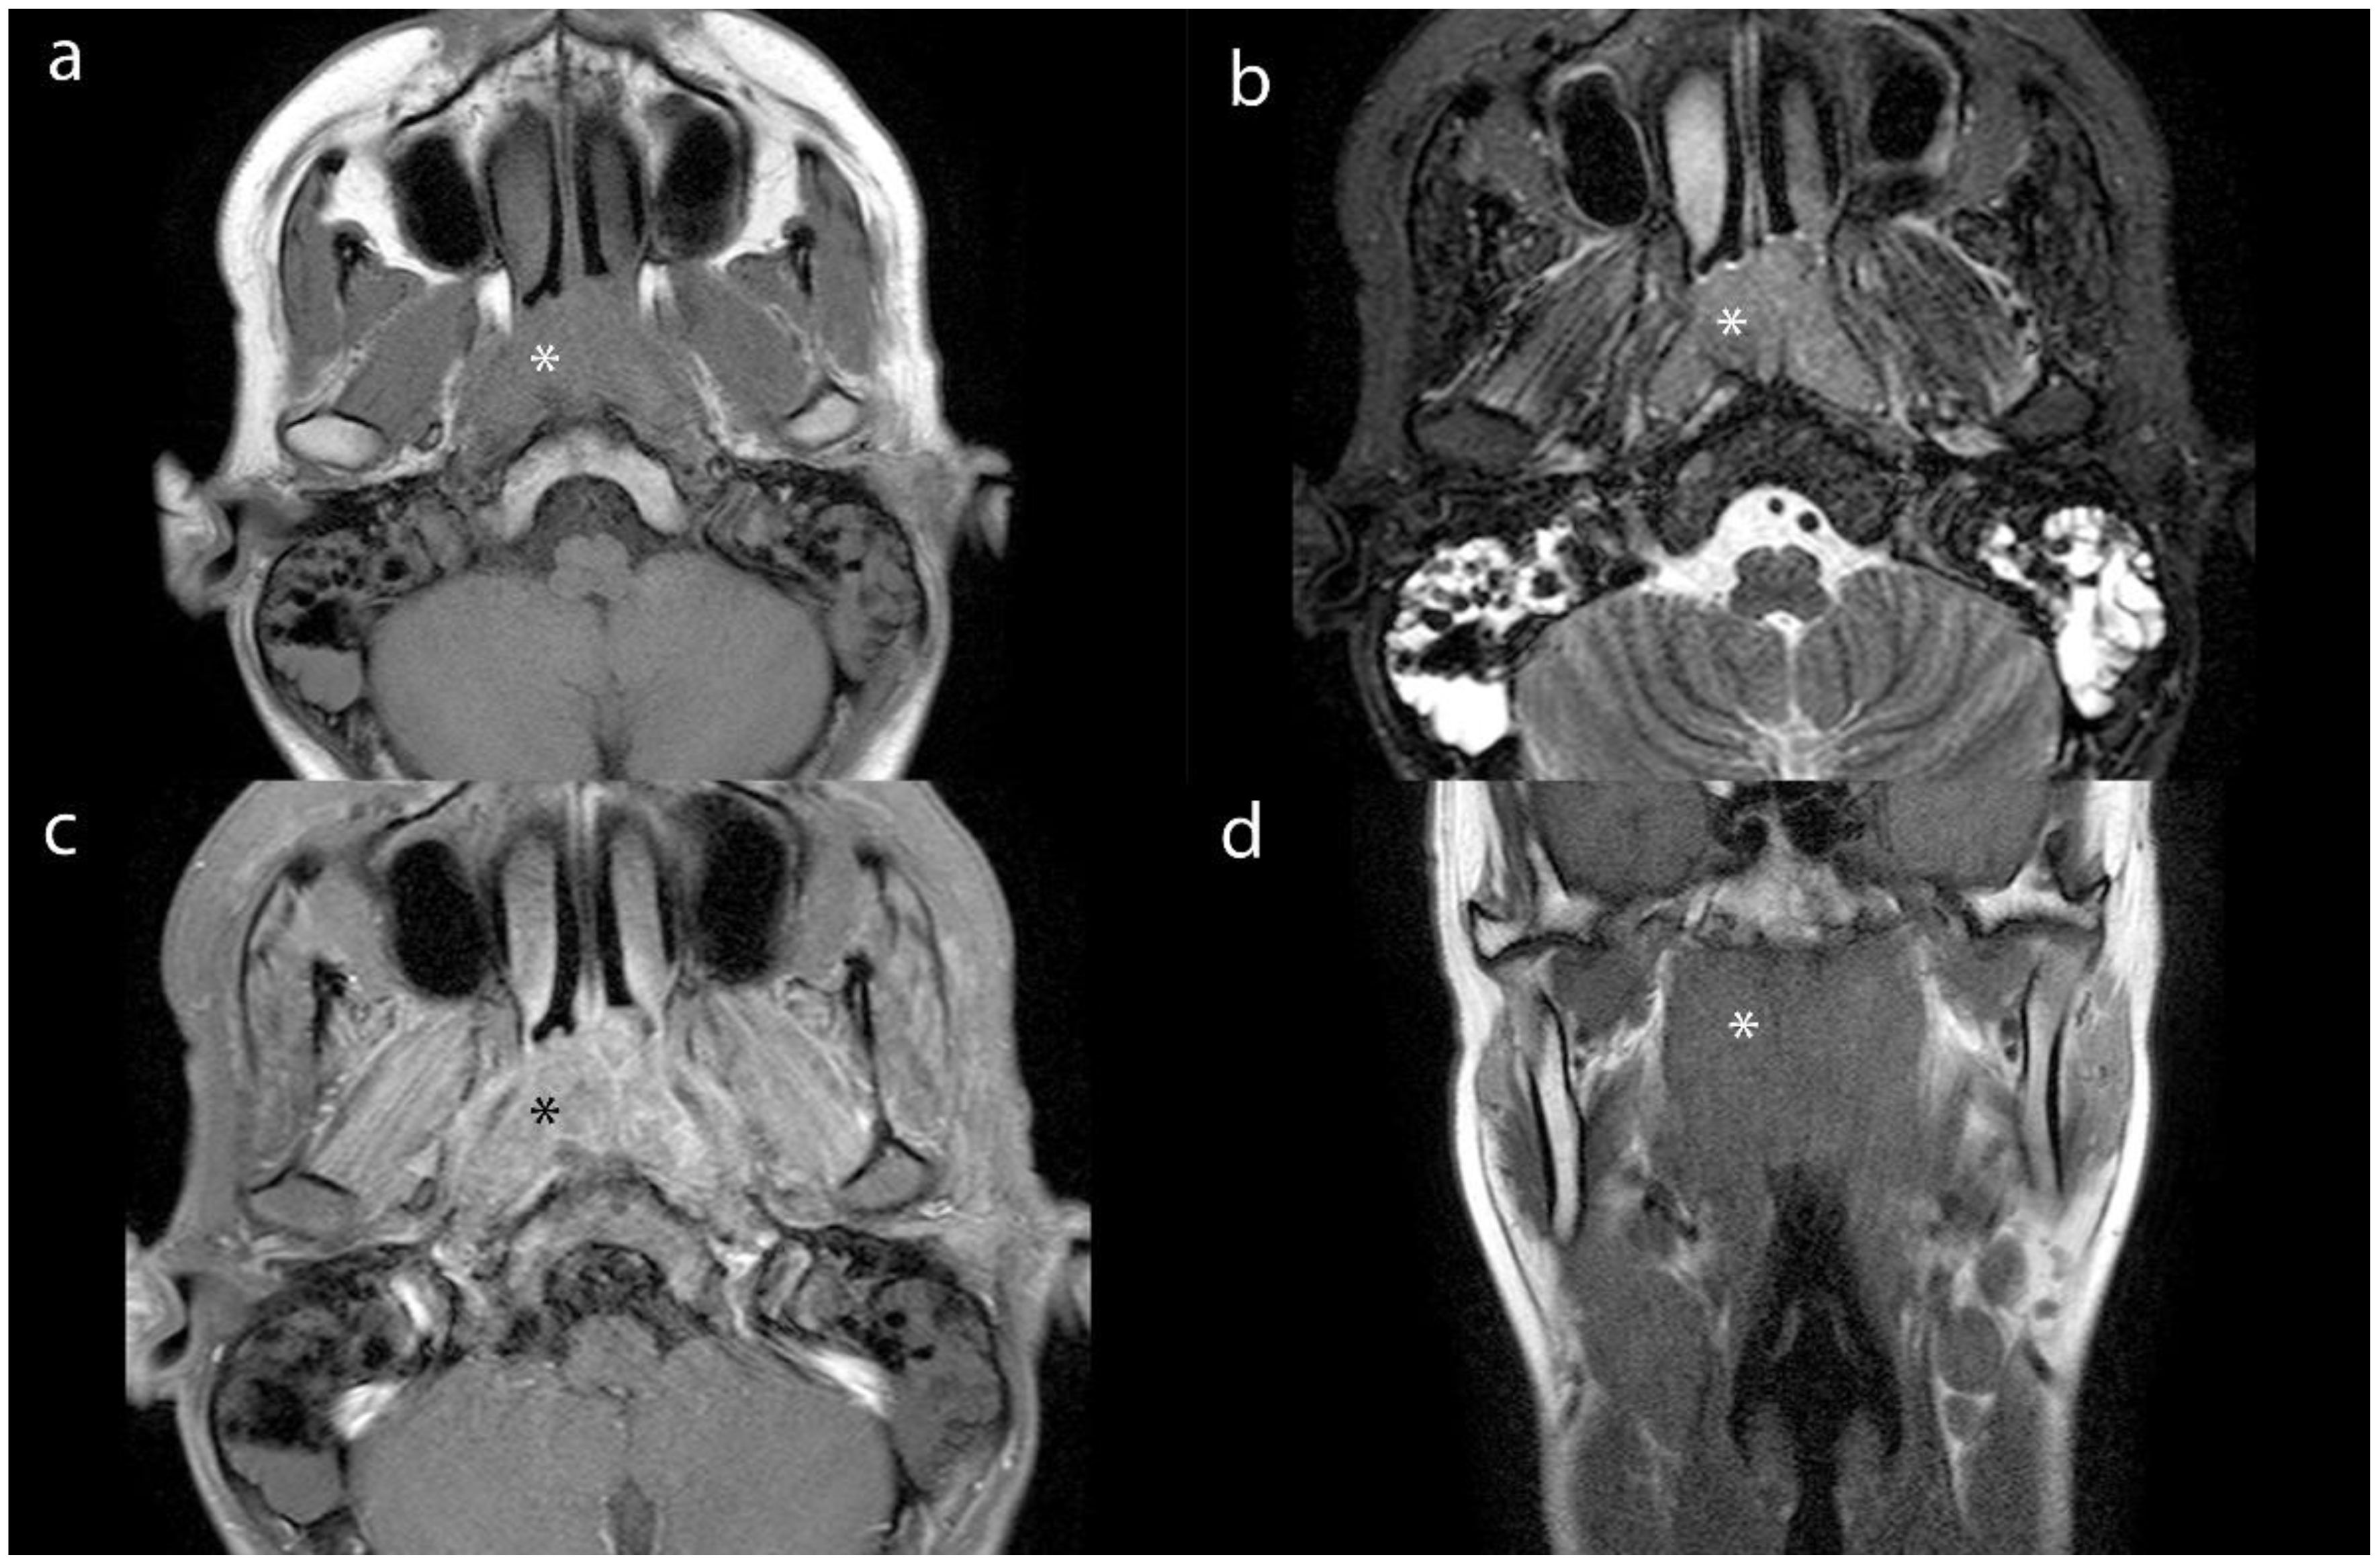

Purpose: To explore the value of dual-energy CT (DECT) in evaluating the efficacy of nasopharyngeal carcinoma (NPC) and in the detection of metastatic lymph nodes (MLNs). Materials and Methods: For this retrospective study, we collected and analyzed clinical and imaging data from 83 patients diagnosed with NPC via histopathology, who were admitted to the Radiotherapy Department from August 2022 to July 2024. The cohort consisted of 64 males and 19 females, with an average age of 50.86±13.45 (years). All patients underwent DECT enhancement and MRI scanning before and after the first treatment course to assess the extent of lesions and lymph nodes (LNs). A total of 423 LN imaging datasets were analyzed. We measured iodine concentration (IC), effective atomic number (Zeff), electron density (ED), and normalized iodine concentration (NIC). Additionally, we recorded the magnetic resonance ADC values of the LNs. Results: Statistical analysis of Zeff, ED, and NIC values of lesion and LNs revealed no significant differences between groups (p > 0.05). The Zeff, ED, and NIC values for lesions and LNs were significantly lower after treatment than before (p < 0.05). Receiver operating characteristic (ROC) analysis for MLNs indicated that the area under the ROC curve (AUC) for NIC indicated high accuracy. Conclusion: DECT provides valuable functional parameters for assessing the efficacy of NPC and demonstrates significant clinical application value. Notably, the NIC parameter shows high diagnostic efficacy for MLNs, comparable to the ADC value obtained from MRI.